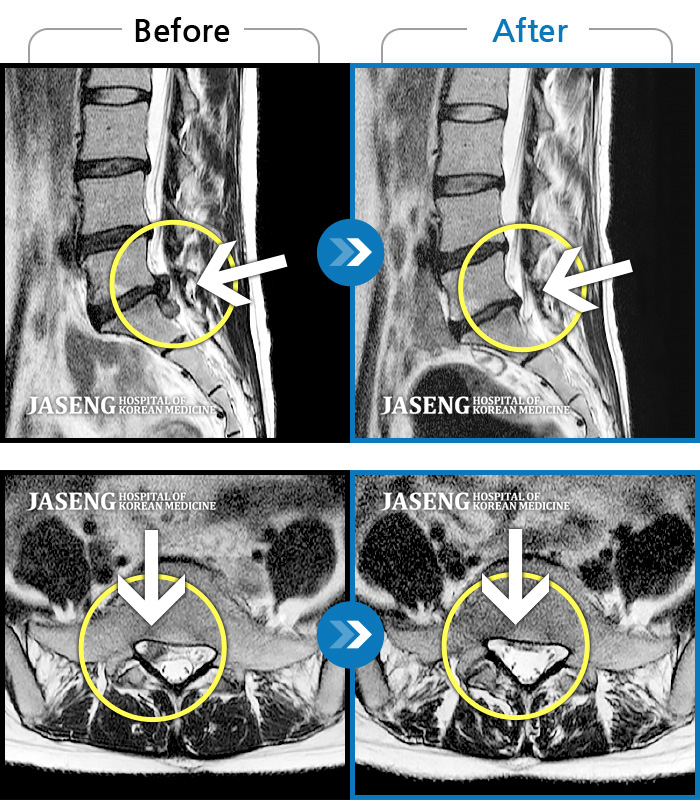

허리 통증 및 우측 골반 저림이 심하여 일상생활이 불편한 상태였습니다.

2023.10.12 ~ 2025.11.21